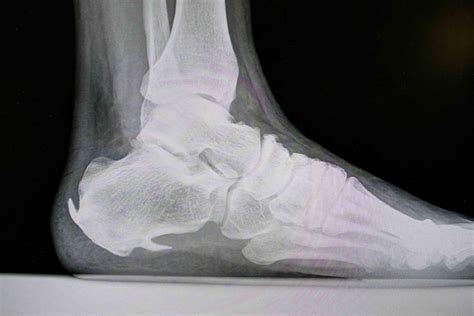

Diagnosing Bone Spurs on Feet

Diagnosing bone spurs on feet typically involves a combination of physical examination and imaging tests. A healthcare provider will:

• Review the patient's medical history and symptoms.

• Perform a physical examination to assess the affected area.

• Order imaging tests such as X-rays, CT scans, or MRIs to visualize the bone spur and determine its size and location.